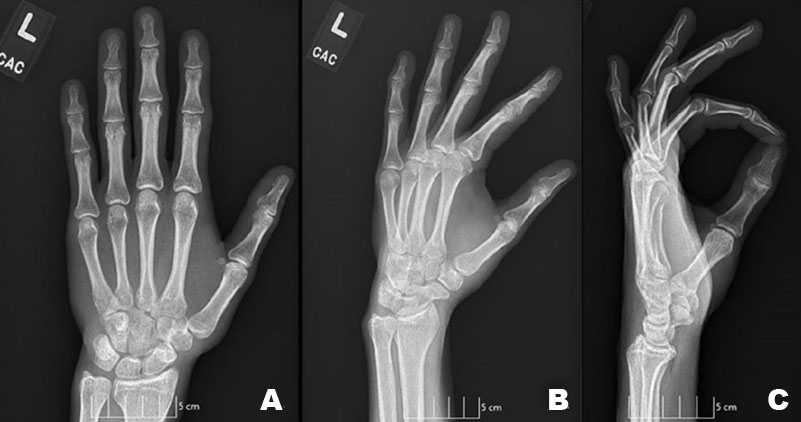

Initially after his incident he arrived at the emergency department where CT scans were taken of the left upper extremity, and interpreted as no acute fracture or subluxation. Two weeks after the inciting event, he presented in our clinic with increased weakness and pain. On physical exam, the patient had diffuse swelling of the left hand and wrist with tenderness over the second and third CMC joints. After clinical examination the patient underwent radiographic evaluation. Anterior posterior (AP), lateral, and oblique views of the wrist and hand were taken and reviewed by a board-certified orthopedic hand surgeon. Lateral view indicated a dislocation of the second and third CMC joints. Further radiographic evaluation showed widening of the second and third CMC joint space, but no accompanying fractures or associated injuries of the hand or wrist (Figure 1).

Figure 1: (A) AP, (B) Oblique, (C) Lateral radiographic views displaying volar dislocation of the second and third metacarpals at the CMC joint of the left hand.